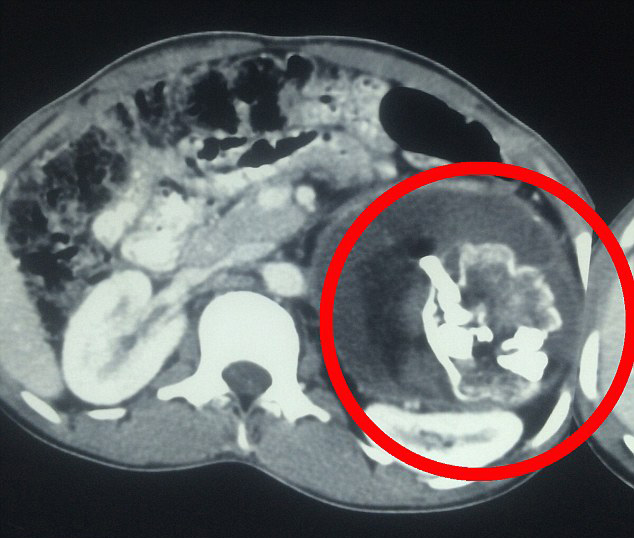

Gencin karnında 2.5 kg ağırlığında kemik, saç ve dişlerden oluşan kütle bulan doktorlar hayretler içinde kaldı. Parazit ikizin, 18 yıl boyunca göbek bağı sayesinde Narendra'nın vücudundan beslendiği ortaya çıktı. Narendra'ya, dünyada şu ana kadar 200 hastada tespit edilmiş 'cenin içinde cenin' teşhisi kondu.

Bu olay, ikiz hamileliğin erken dönemlerinde, bir fetüsün göbek bağı yoluyla diğer fetüse girmesi olarak açıklanmakta. Bu tarz vakalarda parazit fetüs, kardeşinin bedeninden beslenerek hayatta kalmakta.